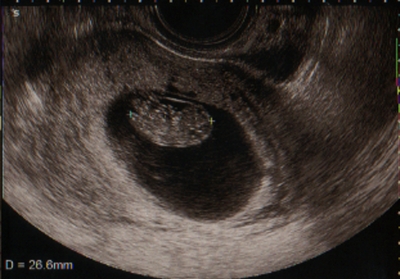

テーマ:赤ちゃん待ち ついにやってきました! 検診(≧∇≦*) 前回の検診から3週間… どれほど不安だったことか…(>_<) 有給休暇を取り、8:30の診療開始に合わせ、受付。 そこから1時間後に診察室へ 先生からは体調の事をちょっと聞かれただけで、すぐに内診室へ。 いつも通り内診台にのり、超音波検査。 すると、カーテンを開け、エコー画面を見せてくれました! 先生「これが赤ちゃんですね〜26.6mm。だいたい9〜10週の大きさなので、平均的ですね。予定日は5/24なの...